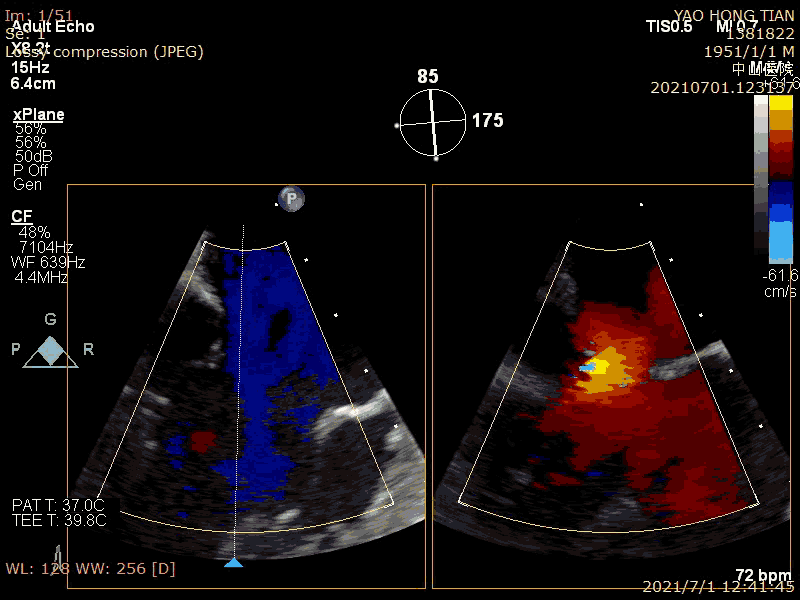

Patient: Male, 70 years old. Preoperative ultrasound diagnosis: Left ventricular ejection fraction (LVEF) 58%, left ventricular end-diastolic diameter (LVDD) 52mm, left atrial diameter (LAD) 57mm, pulmonary artery systolic pressure (PASP) 63mmHg. Severe mitral regurgitation caused by mitral valve leaflet malalignment, vena contracta (VC) 6*13mm, regurgitant area 19.8cm² (Figures 1-2).

Preoperative massive regurgitation (VC 6*13mm)